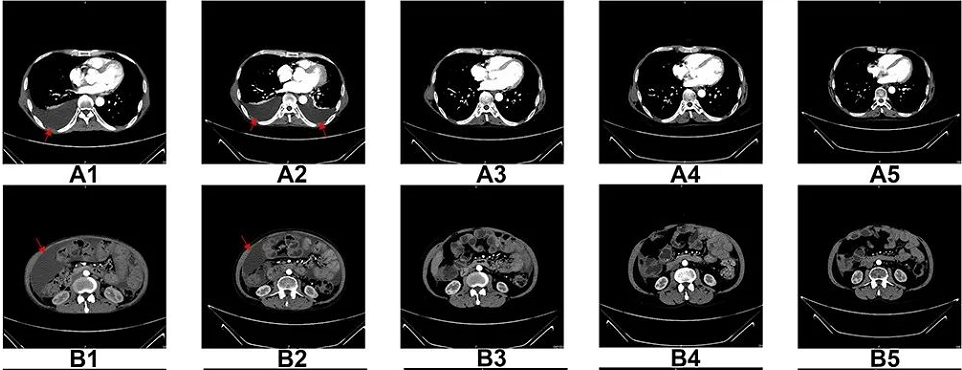

曾有一個 NK 療法治療晚期肝細胞癌的案例刊登在《Oncotarget and Therapy》國外知名雜志上,此案例是一名男性患者,于 2016 年 6 月被診斷為晚期彌漫性肝細胞癌,T3N1M1[即根據腫瘤-淋巴結-轉移(TNM)分期系統的 IV 期]。

從 2017 年 3 月-2018 年 7 月,他完成了 17 個療程的 NK 細胞治療,每個療程每月進行一次,連續兩天輸注。(患者在 NK 細胞治療期間未接受其他治療)

6 個療程后,患者的胸水和腹水明顯減少。自治療結束以來,患者一直保持這種狀態。此外,在 NK 細胞治療 17 個療程后,右肝葉中的多個腫瘤體積減少。

值得一提的是,迄今為止,該名患者的生存時間>48 個月,超過 4 年!

圖A1-A5:CT掃描顯示,6個療程后胸腔積液完全消失

圖B1-B5:CT掃描顯示,6個療程后腹水幾乎完全消失